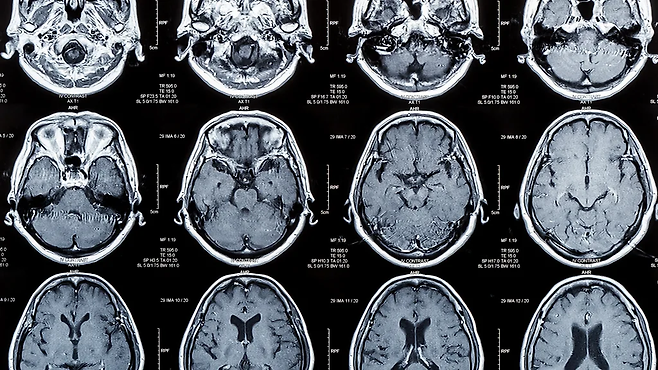

노화가 뇌에 미치는 영향은?

세월이 흐르면서 인간의 뇌 용량은 점차 줄어든다.

특히 일반적으로 전두엽 피질은 뇌에서도 노화로 인해 가장 줄어드는 부분으로, 10년에 약 5%씩 감소한다. 전두엽 피질은 뇌의 다른 부분과 연결돼 있어 마치 온도 조절기나 교향곡의 지휘자처럼 복잡한 정신적 작업을 실행할 수 있도록 도와준다.

그렇기에 전두엽 피질은 지도자의 자질을 얘기할 때 중요한 부분이기도 하다. 문제 해결, 목표 설정, 충동 조절과 같은 부분과 관련 있기 때문이다.

이러한 정신적 작업의 실행 능력은 보통 30대에 접어들면서 서서히 감소하기 시작하는데, 70대가 되면 그 감소 속도가 급격히 빨라진다.

뇌의 백질 부분이 손상되는 백질 질환도 실행 기능 장애의 원인이 되는데, 65세 이상 인구의 약 3분의 1이 이러한 질환을 겪는다. 실행 기능에 문제가 생기면 충동 억제에 어려움을 겪거나 같은 생각 및 행동을 반복할 수 있다.

아울러 뇌 내 다른 구조적 변화도 65세를 전후로 굳어지게 된다. 미국 내 데이터를 사용한 한 연구에선 정신적 작업의 처리 속도가 60세 전후로 느려지기 시작한다고 주장했다.

아울러 뇌에서 노화로 인해 손상된 듯한 부분이 생겼을 경우, 다른 부분이 어떻게 보완해 줄 수 있는지에 관해서도 차이가 있다. 일반적으로 뇌는 매우 가소성이 좋아서 보통의 경우, 한 부위에 지장이 생겨도 다른 부위가 부분적으로 이를 보완하곤 한다. 그러나 알츠하이머병 환자 등 이러한 보완 기능이 떨어지는 사례도 있다는 게 캘리포니아 대학교의 응용신경과학자 마크 맵스톤 교수의 설명이다.

이러한 슈퍼 에이저들의 내후각피질(기억과 관련 있는 뇌 내 영역)은 또래에 비해 더 건강하고 크다. 당연하게도 기억력 테스트에서 이들은 또래에 비해 더 좋은 성과를 낸다.